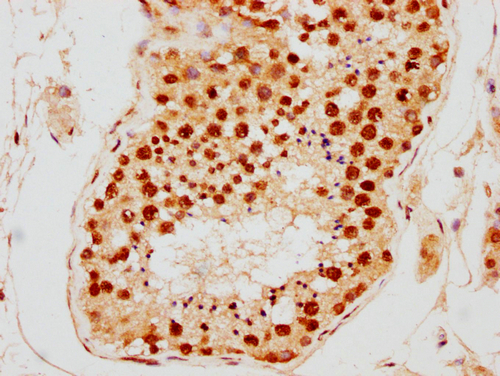

IHC image of CSB-PA010389PA09nsucHU diluted at 1:10 and staining in paraffin-embedded human testis tissue performed on a Leica BondTM system. After dewaxing and hydration, antigen retrieval was mediated by high pressure in a citrate buffer (pH 6.0). Section was blocked with 10% normal goat serum 30min at RT. Then primary antibody (1% BSA) was incubated at 4°C overnight. The primary is detected by a biotinylated secondary antibody and visualized using an HRP conjugated SP system.